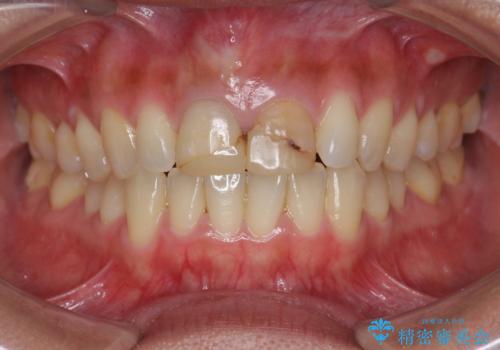

- 3週間後に迫った結婚式までになんとか前歯をきれいにしたいという希望で来院されました。

一回の治療時間を長く取り、限られた時間で最大限の結果を出せるよう集中治療を計画します。

ただ見えるクラウンを白くきれいにするのではなく、長期的な歯の予後を考えると根管治療・ファイバーコア築盛・精密な歯牙形成等クリアすべき条件は多々あると言えます。